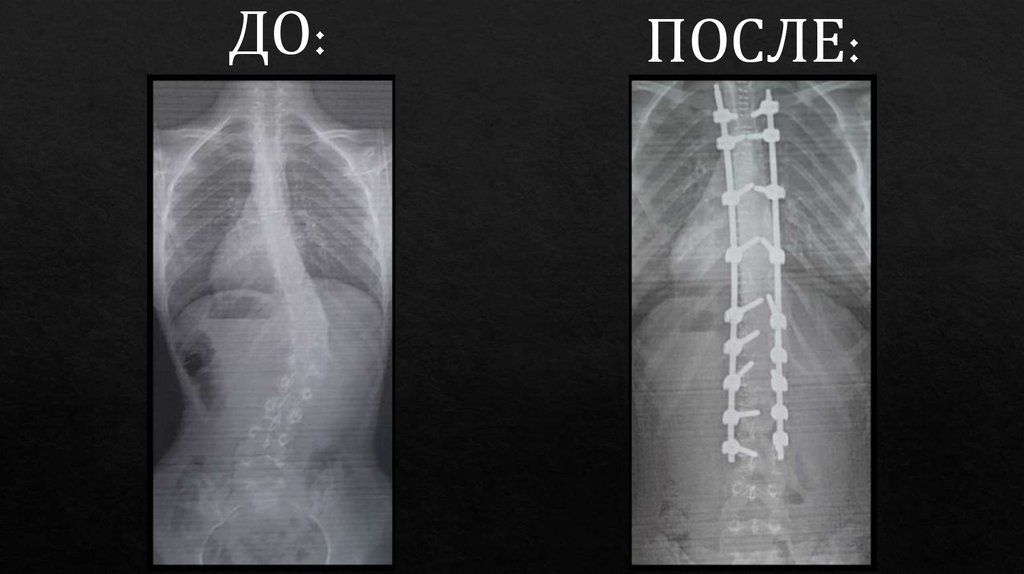

Хирургическое лечение

- Дистракция и кантилеверные методики —

применение специальных систем для

постепенного выпрямления позвоночника и

удержания его в правильном положении.

- Спондилодез — артродез позвоночника, при

котором патологически изменённые позвонки

фиксируются между собой с помощью

металлических конструкций (штифты,

пластины, стержни), что обеспечивает

стабилизацию и устранение искривления.

Хирургическая коррекция показана при выраженных

деформациях с углом искривления более 45-50°, при

проявлениях компрессии нервных структур,

выраженном болевом синдроме и функциональных

нарушениях внутренних органов.

ДО:

ПОСЛЕ: